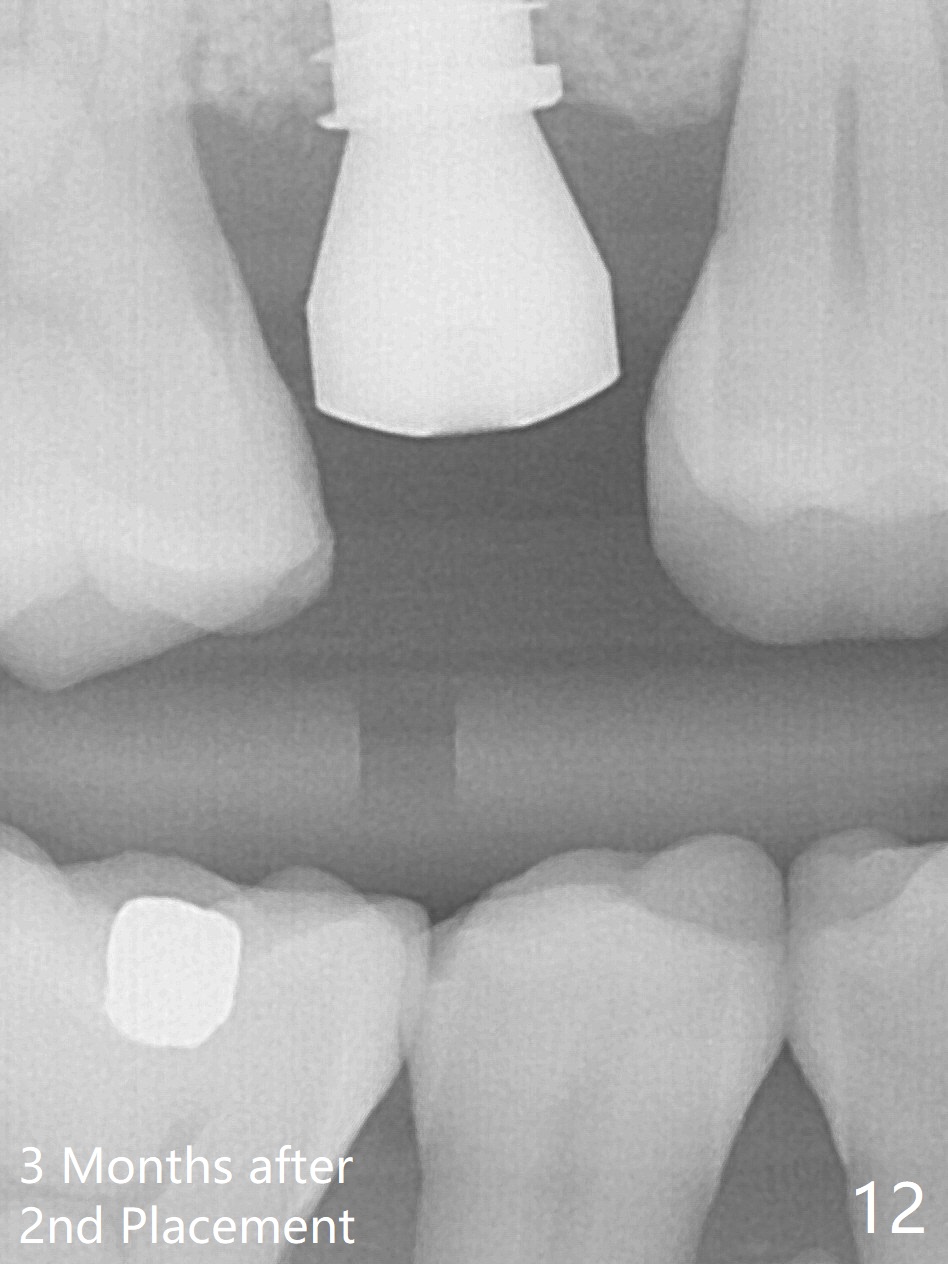

A 47-year-old man returns emergently with subgingival fracture of the lingual (L) cusp of the tooth #4 (Fig.1-3).  After extraction (no bony defect) without drilling, a 4x11 mm dummy implant is placed as a tap drill with satisfactory stability (Fig.4,5).  To get subcrestal placement, a shorter (4x9 mm) implant is inserted with insertion torque of < 35 Ncm.  In retrospect, a larger implant (4.5 mm) would be better in term of primary stability.  After allograft placement into the buccal and lingual gaps, a 4.5x4(4) mm abutment is placed for an immediate provisional.  There is a peri-implant gap 7 months postop (Fig.7<, as compared to the implant at #2 (6 months postop)) .  When the loose abutment is being retightened, the patient feels pain, although the gingiva appears healthy (Fig.8).  A larger implant should have been used; the abutment should have been removed.  The implant dislodges while the abutment is untightened 8 months postop.  The osteotomy is found intact.  A 4.5x11 mm dummy implant is placed 2 mm subgingival with 20 Ncm (Fig.9).  When a 4.5x11 mm definitive implant is placed 3 mm subgingival (Fig.10,11), torque reaches 50 Ncm.  A 5.5x3 mm healing abutment is placed.  Three months postop, the implant is stable (Fig.12,13) and impression is taken.